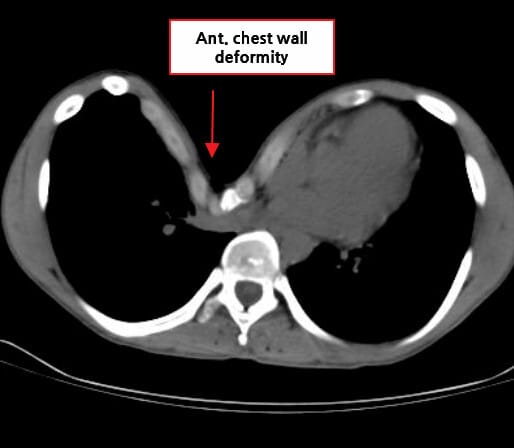

오목가슴증, 흉곽 함몰 (Pectus Excavatum)은 흉골과 갈비뼈 앞쪽 부분이 함몰되며 가슴이 오목하게 들어가는 선천성 흉곽 기형입니다.

흉골이 안쪽으로 들어가면서 흉부 형태가 비정상적으로 꺼지는 구조적 이상으로, 심폐기능에 영향을 주거나 미용적 문제로 수술적 치료를 받는 경우가 많습니다.

| ✅ 흉골이 후방으로 함몰되어 가슴 중앙이 들어간 형태를 보입니다. |

| 🔵 흉부 CT(Chest CT) 및 Haller Index 측정 |

| 횡격막에서 흉골과 척추 사이의 가장 좁은 거리와 가슴의 가로폭을 이용해 Haller 지수를 계산합니다 (Haller index ≥ 3.25 시 수술 고려). |